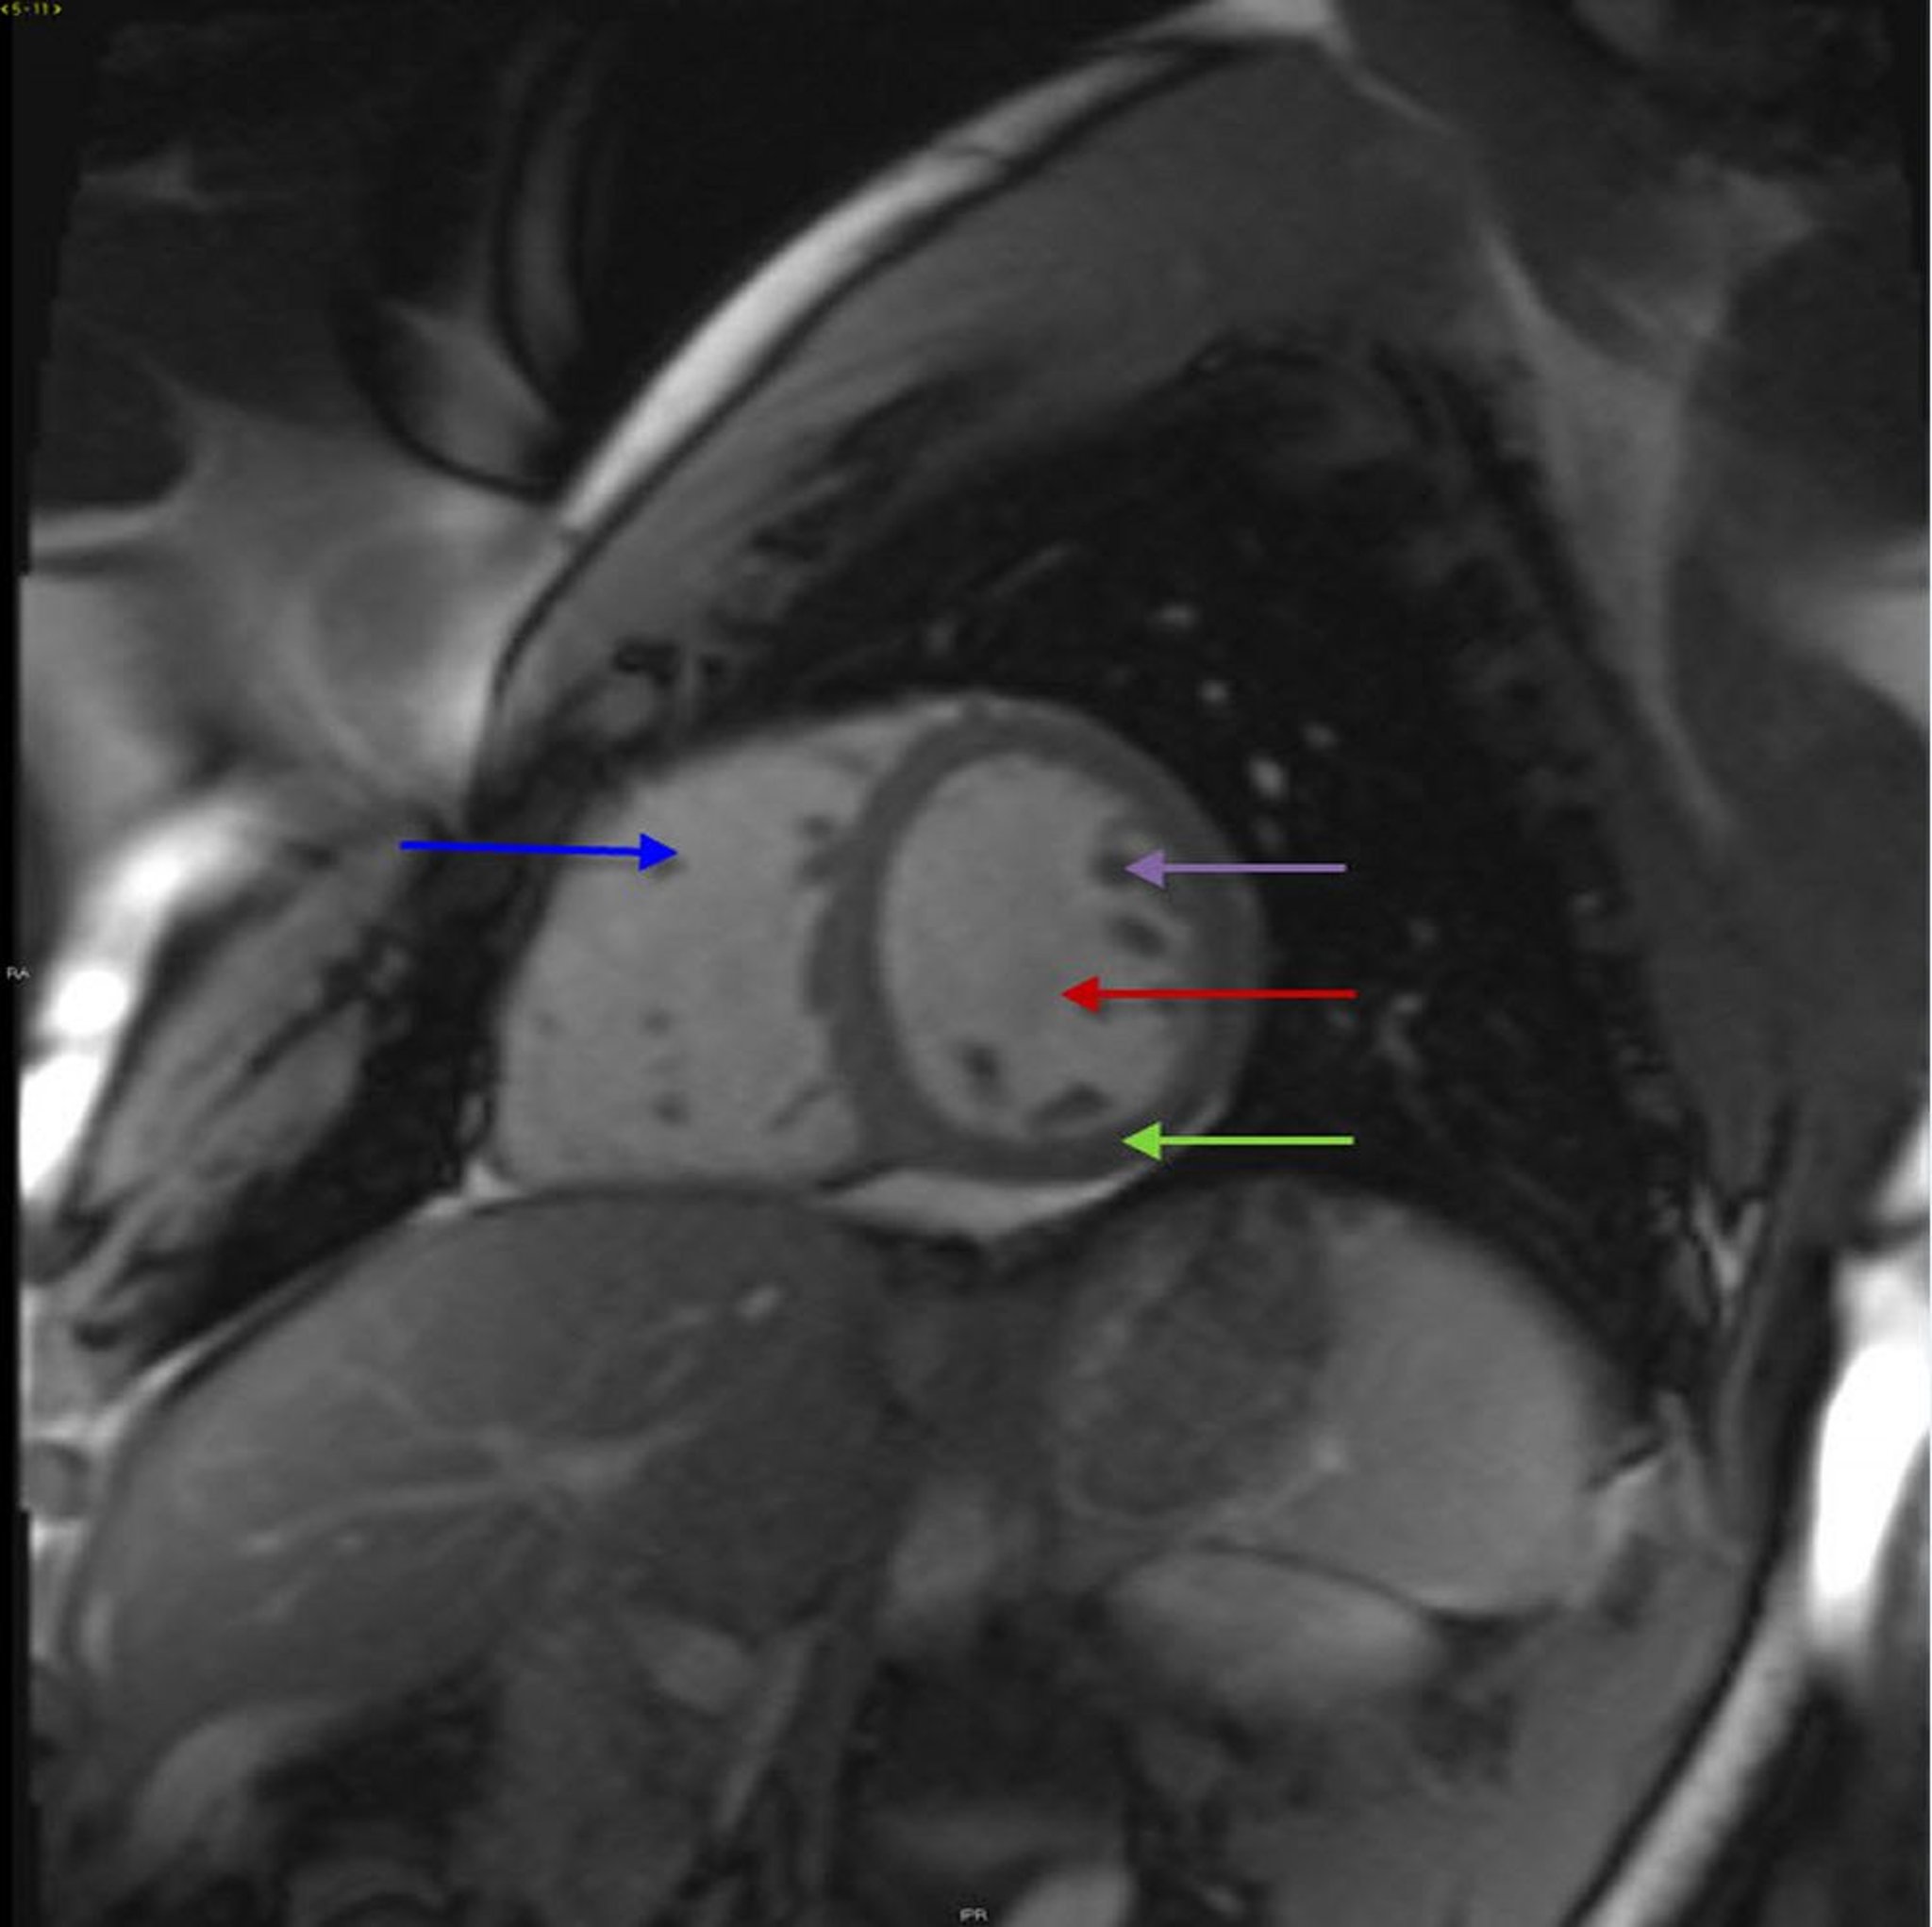

IRM cardiaque montrant une anatomie cardiaque normale

Cette image montre un ventricule gauche (flèche rouge), un ventricule droit (flèche bleue) et un myocarde (flèche verte) normaux. Les muscles papillaires (flèche violette) sont également visibles.